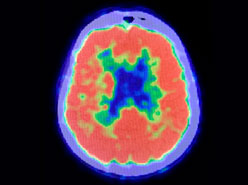

PET (POSITRON EMISSION TOMOGRAPHY)

Positron emission tomography is a test used to visualize the metabolic activity (glucose/sugar use by cells) of the brain. The substance administered during a PET scan is glucose (sugar) tagged with a radioisotope (18F- fluoro-deoxy-glucose). Once administered, a scan is then performed to detect the how much of this radioisotope goes to different parts of the brain. Areas of the brain that are less metabolically active will consume less glucose and will contain lower amounts of radioisotope. Those areas of the brain that consume less glucose (hypometabolic areas) are usually those areas that correspond to the seizure focus. The test is performed on an outpatient basis in the nuclear medicine department. Since this test is sensitive only if performed in the interictal (between seizure) period, it is preferable that the patient undergo simultaneous EEG recording, to make sure that no seizures have occurred before, during, or after the study